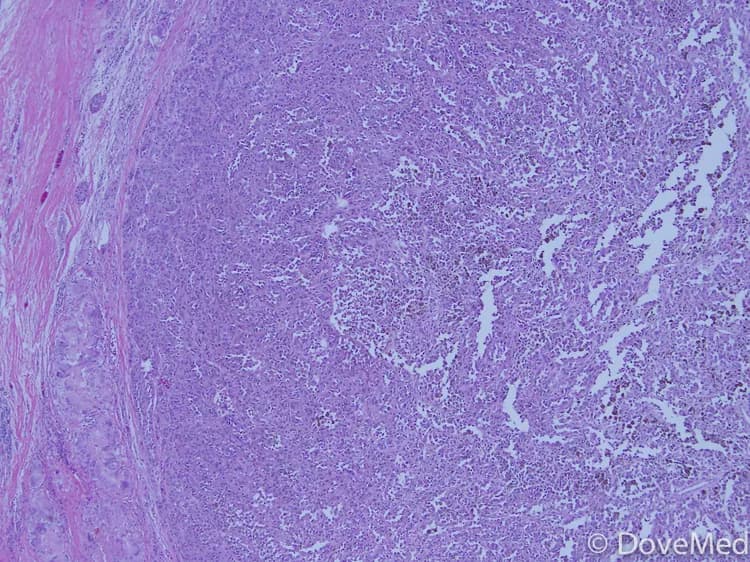

• The tumor can be composed of 2 different types of cells, when looked at under a microscope:

• Spindle-shaped cells

• Epithelioid cells: Epithelioid tumors are more capable of spreading (metastasis)

• Epithelioid tumor cells, as seen under a microscope